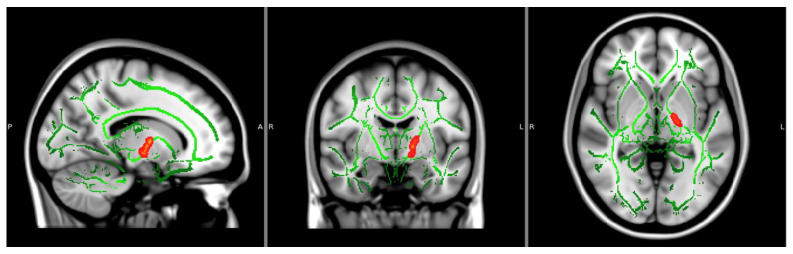

Orientation Dispersion Index: There was a significant main effect of NTP use groupings on ODI values in three distinct clusters, all within the left posterior limb of the internal capsule (ps < 0.05, TFCE corrected), controlling for age and biological sex (see Figure 2 and Table 2). Findings showed larger ODI estimates in NTP use groups compared to the control group (see Figure 3; the figure is only for visualization purposes to help with the interpretation of results). ODI findings continued to be significant after extracting estimates and controlling for past year alcohol use. There were no significant effects of cannabis use groupings or the interaction between NTP and cannabis use groupings.

Table 2: Significant clusters.

| FA Values | Voxels | MAX | MAX X (vox) | MAX Y (vox) | MAX Z (vox) |

| 22 | 0.95 | −23 | −19 | 2 | |

| OD Values | Voxels | MAX | MAX X (vox) | MAX Y (vox) | MAX Z (vox) |

| 39 | 0.958 | −16 | −11 | −5 | |

| 27 | 0.962 | −16 | −5 | 5 | |

| 17 | 0.956 | −21 | −16 | 1 |

Notes: Voxels represent the number of voxels in each significant cluster. Max represents the maximum beta value within the cluster. MAX X/Y/Z is the location of the maximum intensity voxel. FA = fractional anisotropy. OD = orientation dispersion.